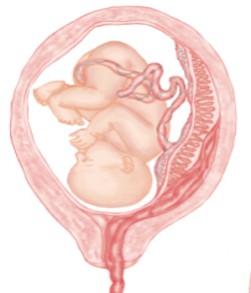

The premature separation of the placenta from the uterine wall before birth, potentially leading to bleeding and hematoma formation on the maternal side of the placenta.

Blood Flows out

Hematoma